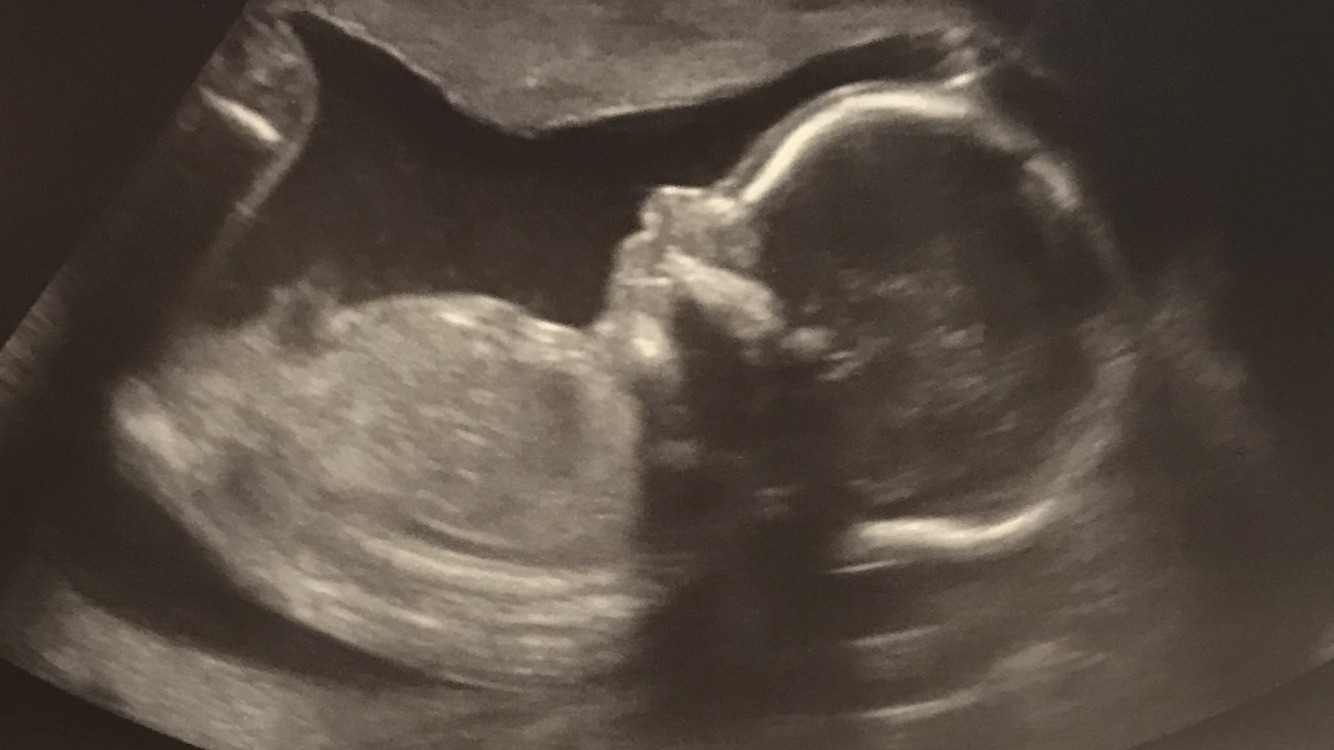

20 weeks in this ultrasound. We are not finding out gender but just wanted to see what y’all though about skull :)

If I had to make a guess based on skull I'd guess boy, but it's really not a reliable method.

We had a girl!!! :)